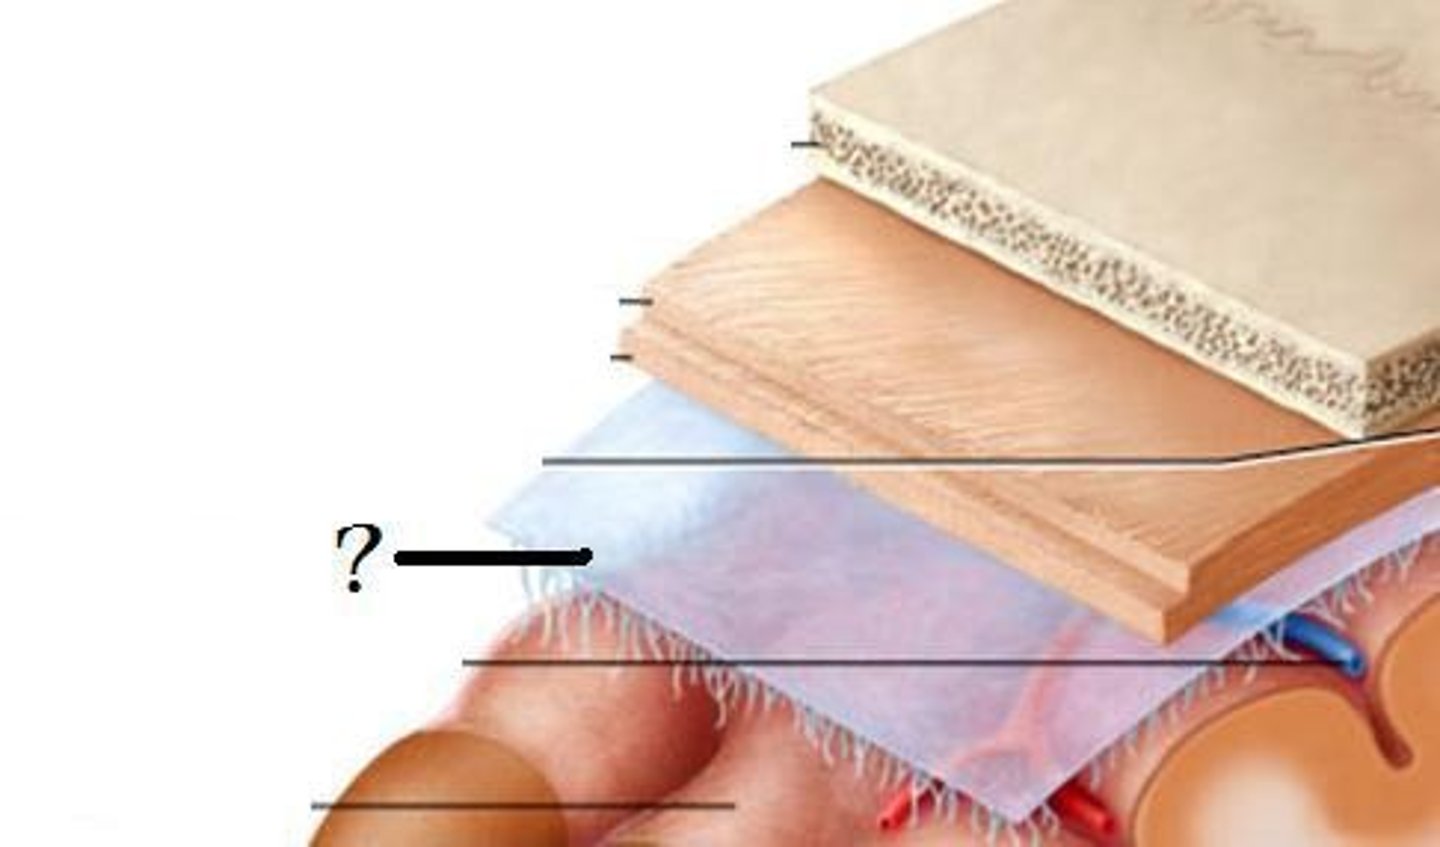

arachnoid mater

dura mater

pia mater

subdural space

epidural space

subarachnoid space